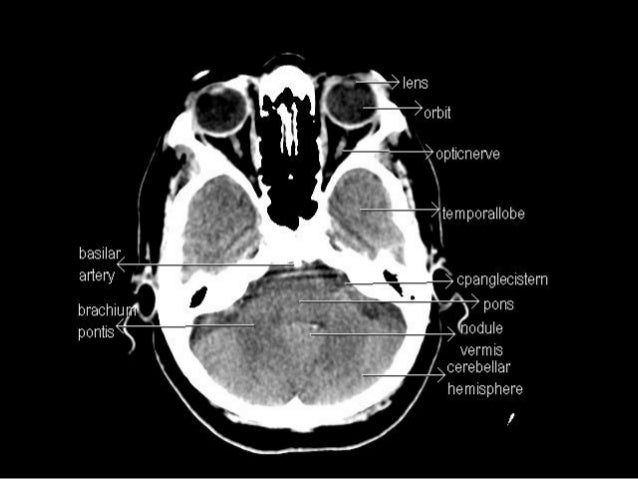

This video is from our cross sectional anatomy series. Cranial cross sectional anatomy is very important to know prior to analyzing a head ct.

Ct cross sectional anatomy. Only 9 left in stock order soon. Ct cross sectional anatomy of brain chest abdomen paranasal sinusus neck temporal bone heart slideshare uses cookies to improve functionality and performance and to provide you with relevant advertising. Symmetry is an important concept in anatomy and is almost always present in a normal head ct unless the patient is incorrectly positioned with the head cocked at an angle.

Once the normal structures are identified abnormalities can be detected and a diagnosis may be possible. Cross sectional anatomy timothy f. Cross sectional anatomy ct mri by govind b.

The Radiology Assistant Brain Anatomy

The Radiology Assistant Brain Anatomy